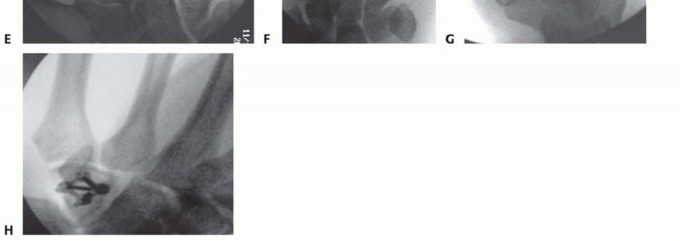

Clinical & Radiographic Imaging Archive